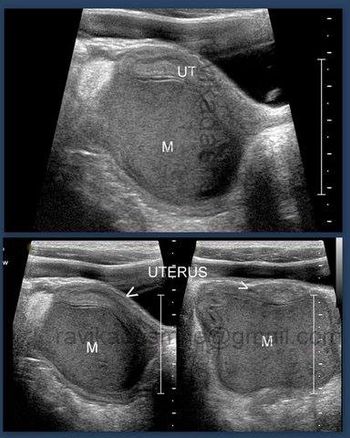

New research shows that symptoms exist in even early-stage ovarian cancer, disproving the myth that it's a "silent killer." Barbara Goff, MD, presents the latest in symptom research, tips on what physicians should be looking for, and what's on the horizon for ovarian cancer screening.